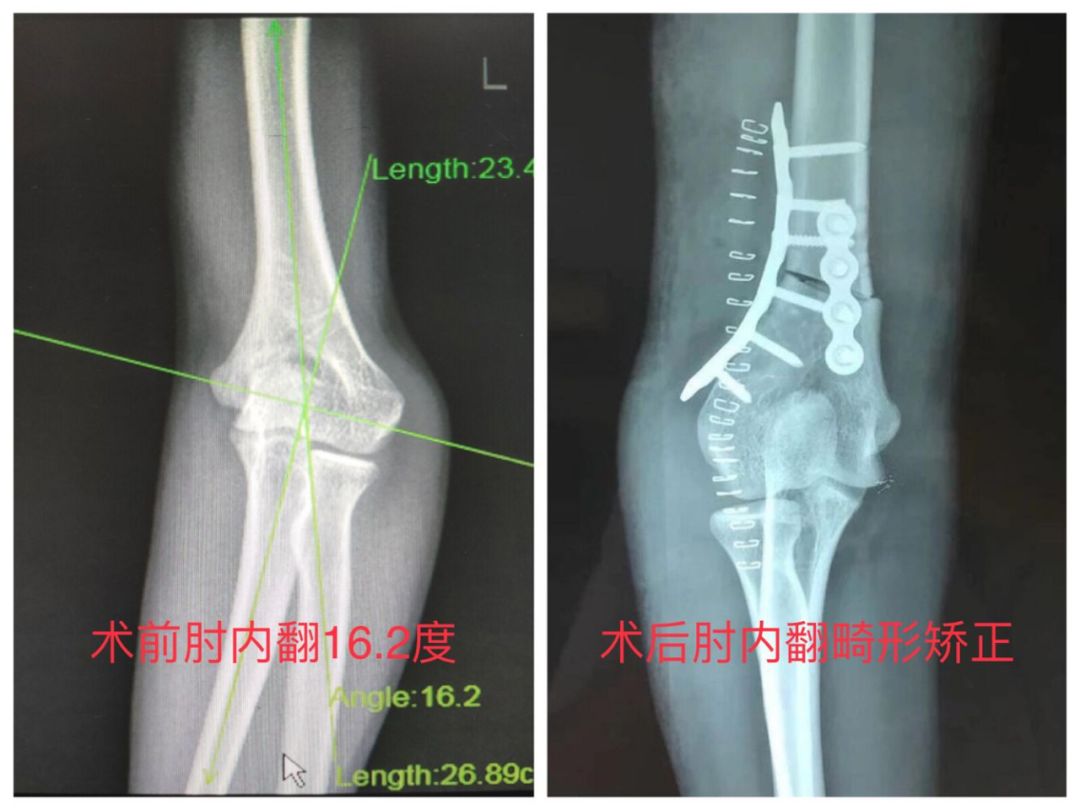

矫形手术治疗骨折畸形患者 冀中能源峰峰集团总医院 微信公众号文章阅读 Wemp

家长讳疾忌医导致孩子手臂畸形 现在后悔莫及 知乎

家长坚持不手术胳膊摔骨折五岁男孩胳膊肘 向外拐